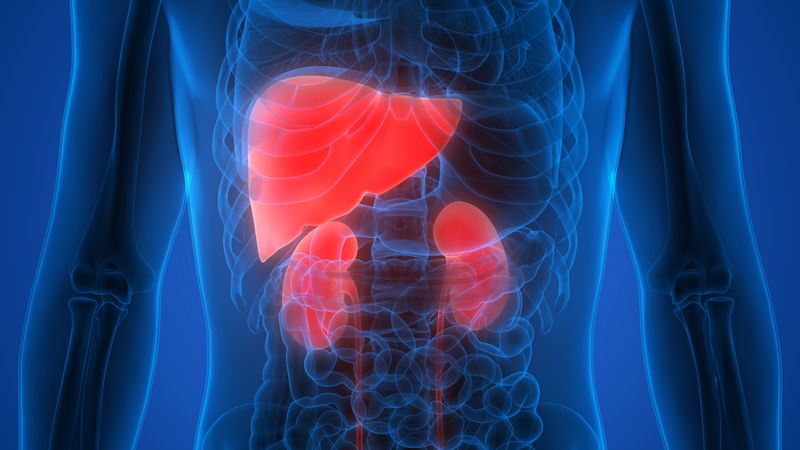

At least two people in the trial died after taking the drug, according to media reports by STAT News and Science. One of these fatalities was a 65-year-old woman who died from a massive brain hemorrhage that some researchers link to the drug. The other was a man in his late 80s who was taking a blood thinner for a heart condition.

Paired with these two deaths, the data from the trial shows that six lecanemab-treated patients suffered from strokes.

“Recent reports of two deaths from strokes, attributed to a side-effect of the drug, are concerning. The data published today indicate that six lecanemab-treated patients suffered strokes during the trial compared with two in the placebo group. Treatment, therefore, does carry risks, and in some rare cases this can be severe or life-threatening,” commented Rob Howard, Professor of Old Age Psychiatry at UCL, who was not involved in the research.